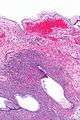

| Micrograph showing a mucinous cystadenoma of the ovary. H&E stain. | |

Mucinous cystadenoma is a benign cystic tumor lined by a mucinous epithelium. It is a type of cystic adenoma (cystadenoma).

Mucinous cystadenomas make up 15-20% of all ovarian tumors. They often become very large and can extend up into the abdomen.

Benign mucinous cystadenomas compose 80% of mucinous ovarian tumors[2] and 20-25% of benign ovarian tumors overall. The peak incidence occurs between 30-50 years of age. Benign tumors are bilateral in 5-10% of cases.